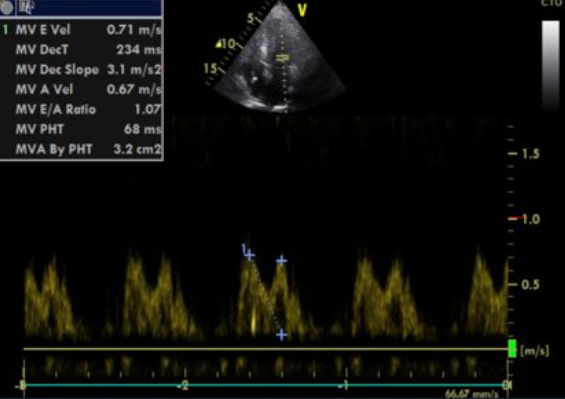

- TTE: concentric and symmetric hypertrophy with ‘granular sparkling’ appearance with diastolic dysfunction and valvular thickening associated with atrial dilatation and thickening of the interatrial septum.